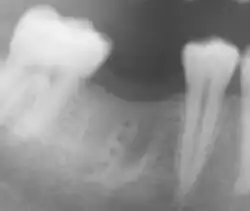

Absolute Indikation: Querfraktur der Zahnwurzel im mittleren Drittel der Zahnwurzel. Nebenbefund: Approximal-Karies

Relative Indikation: Der Zahn 37 könnte evtl. nach einer Wurzelbehandlung mit einer Krone erhalten werden. Nebenbefunde: Der Zahnkeim 38 ist retiniert und verlagert. Der Zahn 27 ist stark kariös.